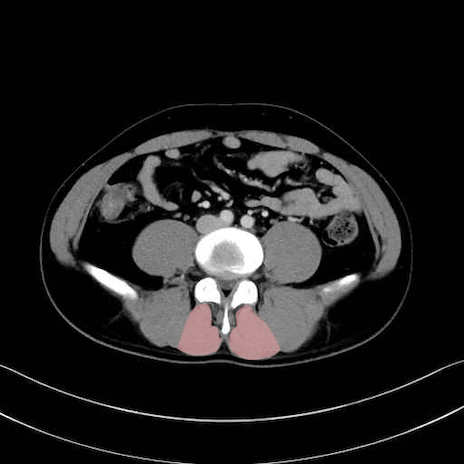

多裂筋 (Multifidus)